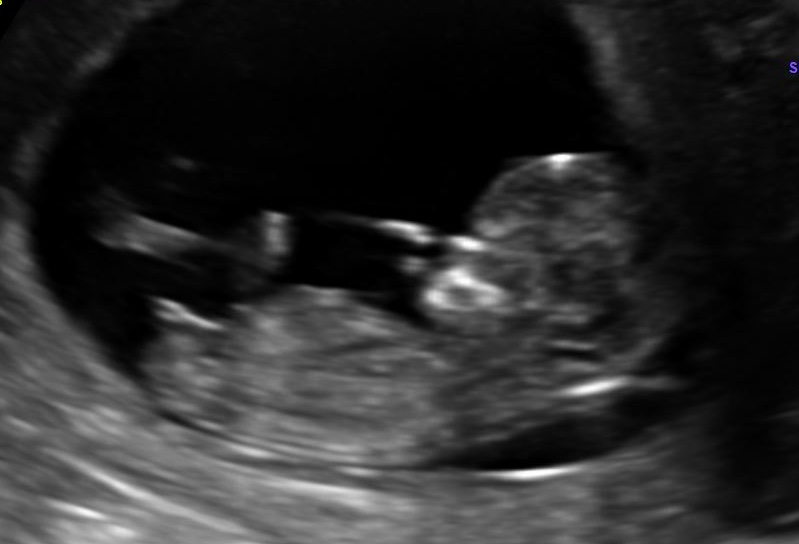

Can you tell by this pic if the nub looks like a boy or girl? I have other ones if this one isn't good, Thanks!

The top pic leans girly, but there’s still time for it to rise. I don’t see anything clearly in the second pic. I’m not a huge fan of using nub theory from a single still shot versus viewing a live scan.

I’d lean girl but given the gestation there is still plenty of time for development into a boy nub.

Too early to tell unfortunately. If you were closer to 13 weeks I’d say girl, but there’s still time for the nub to rise.

Yep, too soon for me. The genitals aren't reliably obviously different till the end of the twelfth week and more reliably into the 13th. All boys start off looking like girls, so if you guess too early, you can be tricked into thinking a boy is a girl (which can be very upsetting!)